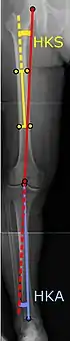

Angles commonly measured before knee replacement surgery:

• Hip-knee-shaft angle (HKS)[10]

• Hip-knee-ankle angle (HKA)[11]

To indicate knee replacement in case of osteoarthritis, its radiographic classification and severity of symptoms both should be substantial. Such radiography should consist of weightbearing X-rays of both knees: AP, lateral, and 30 degrees of flexion. AP and lateral views may not show joint space narrowing, but the 30-degree flexion view is most sensitive for narrowing. Full-length projections also are used in order to adjust the prosthesis to provide a neutral angle for the distal lower extremity. Two angles used for this purpose are:

• Hip-knee-shaft angle (HKS),[10] an angle formed between a line through the longitudinal axis of the femoral shaft and its mechanical axis, which is a line from the center of the femoral head to the intercondylar notch of the distal femur.[12]

• Hip-knee-ankle angle (HKA),[11] which is an angle between the femoral mechanical axis and the center of the ankle joint.[12] It is normally between 1.0° and 1.5° of varus in adults.[13]